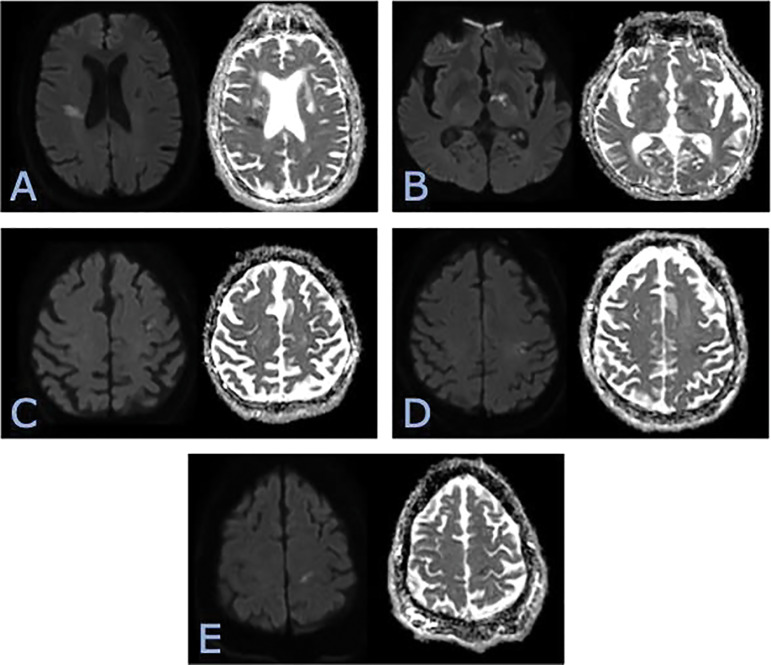

Objective: Stroke is a leading cause of global disability and mortality, a burden projected to grow as populations age worldwide. Early recognition and our ever-advancing interventions can substantially change outcomes and final costs. This has warranted adapting strategies that maximize sensitivity, including a lower threshold for code stroke imaging. This growing demand requires matching resources, an issue that is particularly noticeable in community hospital settings. The National Institutes of Health Stroke Scale (NIHSS) is a well-established quantitative tool for guiding clinical management. This study aimed to assess the availability and applicability of the NIHSS at the time of imaging for code stroke evaluations in a community hospital setting and in comparison to the previous studies conducted in tertiary academic centers. Materials and methods: We performed a retrospective analysis of all code stroke activations at a community Level 1 stroke center from October 2021 to September 2023, when institutional benchmarks were last adapted. All patients underwent non-contrast head CT, CT angiography of the head and neck, and subsequent brain MRI. Data collected included NIHSS documentation status, door-to-CT and door-to-NIHSS times, imaging positivity, final neurological diagnosis, and therapeutic interventions. Statistical analysis included descriptive statistics, t-tests, and receiver operating characteristic (ROC) analysis using NIHSS to predict positive strokes. Results: A total of 291 patients were included (151 women, 140 men). NIHSS documentation prior to imaging was available in 61.2% of cases. Median door-to-CT time was 12 minutes, while median door-to-NIHSS time was 29 minutes. Imaging was positive for acute stroke in 33.6% of cases. Patients with NIHSS documented prior to imaging had a higher stroke positivity rate (36.5% vs 28.0%; odds ratio [OR] 1.45 (95% CI 0.86-2.42). The mean NIHSS among all patients was 6.3, and higher scores correlated with positive imaging (mean 9.1 vs 3.7). ROC analysis for NIHSS predicting imaging positivity yielded an AUC of 0.69. Notably, eight patients (2.7% of all patients) had an NIHSS of 0 but demonstrated acute infarcts on imaging. Conclusion: Our findings demonstrate that NIHSS documentation often lags behind imaging in a community setting, yet its availability can provide useful prognostic information. Higher NIHSS scores correlate with a higher number of positive strokes by imaging, yet, strokes may be seen even with an NIHSS score of 0. These findings emphasize maintaining a low threshold for imaging and the importance of prompt NIHSS documentation, especially in community stroke centers increasingly relying on tele-neurology.